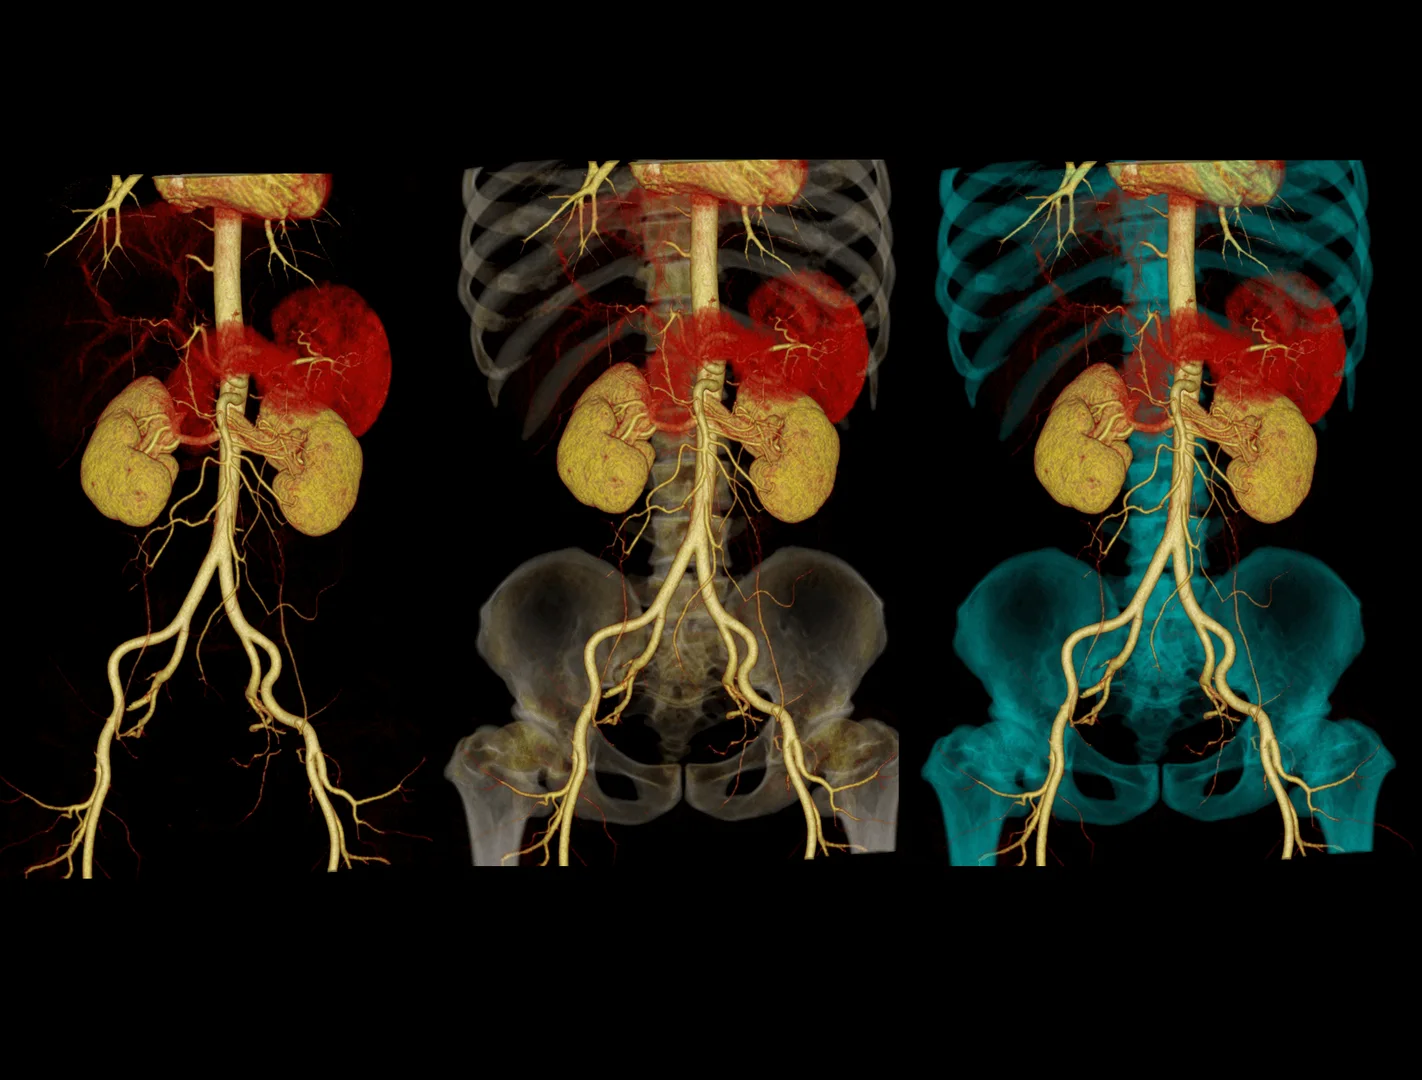

- Angio-TAC: sistema vascular